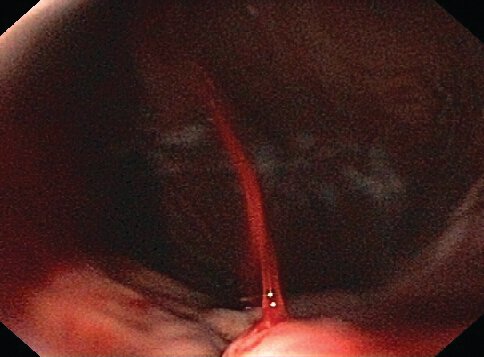

identify and what is the timeline for treatment?

Acute esophageal variceal hemorrhage. A varix in the distal esophagus is seen spurting bright red blood.